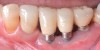

Dental implants have revolutionized the way in which clinicians treat and restore partially and fully edentulous patients and have demonstrated success for managing a broad range of clinical dilemmas. While implants have been highly predictable and have achieved long-term success, they are not immune from complications associated with improper treatment planning, poor surgical and prosthetic execution, material failure, and inadequate or infrequent maintenance. Among these problems are the biologic complications of peri-implant mucositis and peri-implantitis, which are inflammatory conditions in the soft and/or hard tissues surrounding dental implants (Figure 1 through Figure 4).1,2

Fig 1. Clinical view of severe gingival inflammation with possible early bone loss present around the implant at the site of the maxillary left first molar. The two premolar implants had mucogingival deformities.

Figure 1